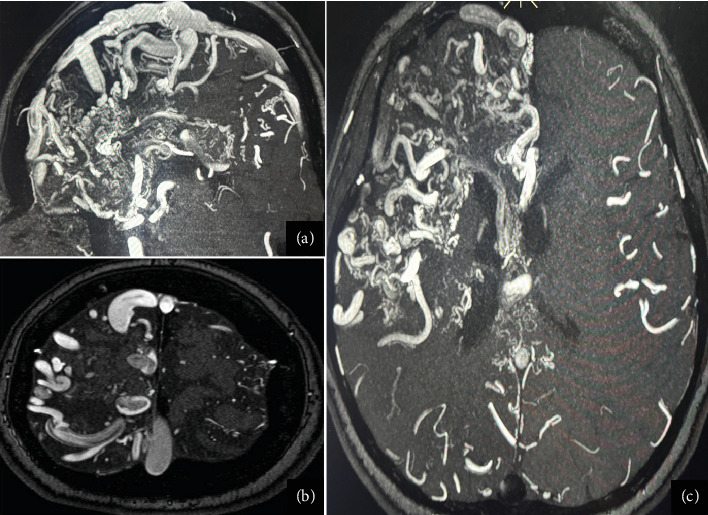

颅内动静脉畸形(AVMs)是一种血管异常,可表现为颅内出血、癫痫发作或神经功能缺损。在本病例中,我们报告了一名6岁时因脑出血而被诊断为巨大右额顶叶AVM (Spetzler-Martin Grade V)的女性。由于病变的大小和明显的位置,手术、血管内和放射外科治疗都不可行。随着时间的推移,患者出现局灶性癫痫发作,包括先天性畸形和左臂痉挛性单眼。最初的抗癫痫药物如卡马西平和苯妥英在最佳剂量下不能提供足够的控制,苯妥英加剧了癫痫发作的频率。通过左乙拉西坦和卡马西平的联合治疗,最终实现了部分癫痫发作的控制。神经影像学显示大的动静脉畸形,脑电图显示局灶性癫痫样活动。这个病例说明了治疗巨大心房动静脉畸形继发癫痫的复杂性,强调了个体化心房动静脉畸形策略和协作、多学科管理的必要性。

Intracranial arteriovenous malformations (AVMs) are vascular anomalies that can present with intracranial hemorrhage, seizures, or neurological deficits. In this case, we present a woman with a giant right frontoparietal AVM (Spetzler-Martin Grade V) initially diagnosed after an intracerebral hemorrhage at Age 6. Surgical, endovascular, and radiosurgical treatments were not viable due to the lesion's size and eloquent location. Over time, the patient developed focal seizures, including catamenial patterns and left-arm spastic monoparesis. Initial antiseizure medications (ASMs) such as carbamazepine and phenytoin failed to provide adequate control at optimal dosage, with phenytoin exacerbating seizure frequency. Partial seizure control was eventually achieved with a combination of levetiracetam and carbamazepine. Neuroimaging showcases a large AVM, while EEG revealed focal epileptiform activity. This case illustrates the complexity of treating epilepsy secondary to giant AVMs, emphasizing the need for individualized ASM strategies and collaborative, multidisciplinary management.